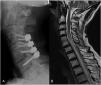

We present a case of a 75-year-old male who underwent an esophageal dilation procedure and developed afterward a spondylodiscitis with epidural abscess due to a neglected esophageal perforation. Blood cultures were positive for Peptostreptococcus. Cervical spondylodiscitis and epidural abscess are extremely rare complications of esophageal dilations. Successful treatment without debridement was achieved by performing a posterior fixation without decompression associated with antibiotic therapy for 8 weeks. The present case highlights that spondylodiscitis and epidural abscess may be treated in selected cases where the anterior neck is unapproachable and with a recognized pathogen by a posterior approach fixation without debridement, in association to specific antibiotic therapy.